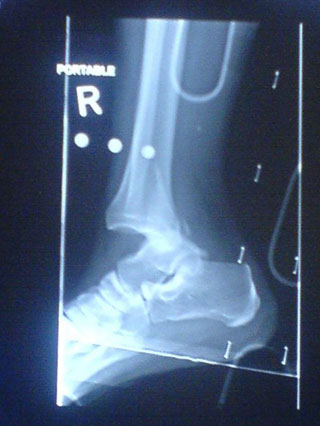

MTBランでクラッシュや故障はつきもの。しかし世の中には凄い乗り方をする強者がいるもの。「こんなのあり?級」の珍しいダメージ画像を集めてみました。